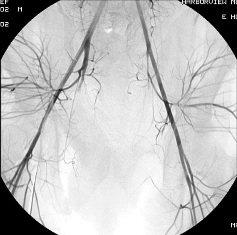

女性盆腔血管分布图

女性盆腔血管分布主要:是膀胱、生殖器官和直肠、是植物神经功能紊乱、事站立工作、子宫后位、长期便秘、早婚早育、孕产频繁的人,以及患有盆腔炎、附件炎、子宫内膜炎等炎症时,静脉血流量增多,盆腔静脉压力增高,影响静脉回流,也容易导致充血。 一般女性在性兴奋时,大量血液涌入盆腔组织,形成充血状态。如果未能达到性高潮,则盆腔充血状态消退很缓慢,会出现下腹坠胀、酸痛等不适。